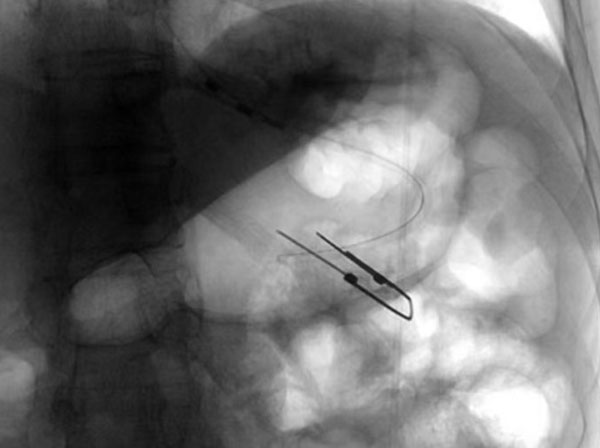

没有营养支持,患者无法进一步治疗,建立肠内营养通路迫在眉睫。放射科介入团队创新性提出全麻护航的手术方案,杨光主任与麻醉科沟通后,为患者制定了个体化镇静镇痛策略,同时采用联合DSA透视下的精准引导,快速将导丝及导管经口鼻迅速置入胃腔内,短时间内精准定位穿刺点,操作时间仅用15分钟。患者术中无不良反应,术后5分钟即恢复意识,造瘘管引流通畅,实现了全程无痛介入。